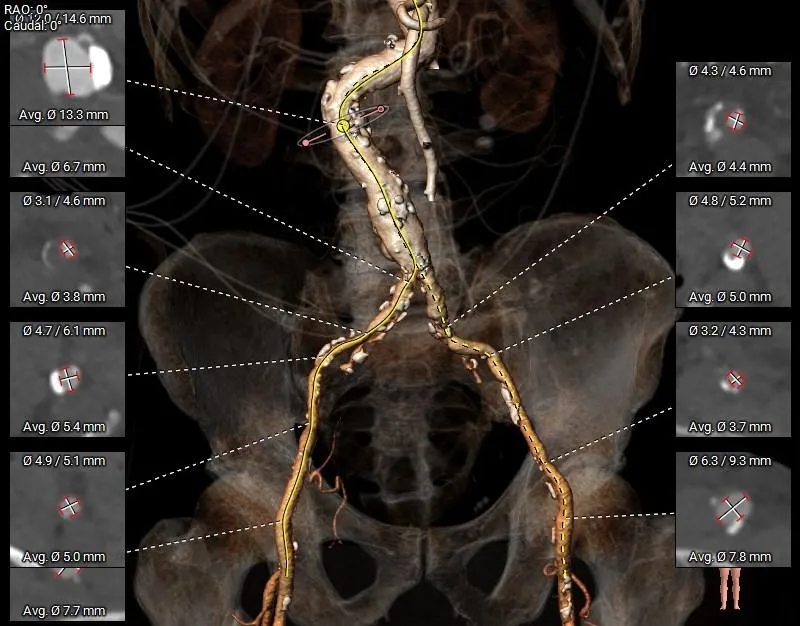

术前CT分析

-

三叶瓣,系纯反流患者,环周长折算直径24.7mm;

左冠开口高度约为8.4mm,右冠开口高度18.5mm;左右冠脉风险相对较低;

瓣环角度约为55°,主动脉弓距尚可,走形尚可,升主明显增宽,左室收缩末期明显增大;

左右重叠体位:RAO 22° CAU 40° ,左冠切线位:LAO 23° CRA 17°;

左右股动脉条件较差,左右髂动脉均局部狭窄,注意血管入路风险。

主动脉根部测量

Annulus

24.7mm

LVOT

26.2mm

VR图

SOV:

41.0*40.9*47.6mm

STJ:

39.1mm

AAO:

40.1mm

瓣上结构测量

瓣上2mm

瓣上4mm

27.4mm

瓣上6mm

29.6mm

瓣上8mm

33.9mm

外周入路评估